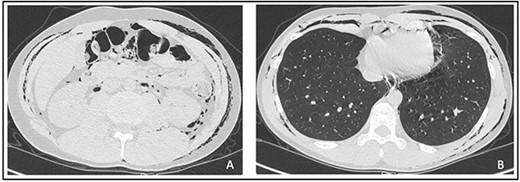

An abdominal and thorax computed tomography (CT) scan showed subcutaneous emphysema in the thorax, neck, abdomen, back, scrotum and intergluteal fold along with a pneumomediastinum (Fig. 2A and B).

Signs neither of pulmonary embolism or pneumothorax nor free intraperitoneal gas were detected. Considering stable vital parameters, we opted for clinical observation in our department. The patient was discharged 3 days after with an almost completed reabsorption of the emphysema.